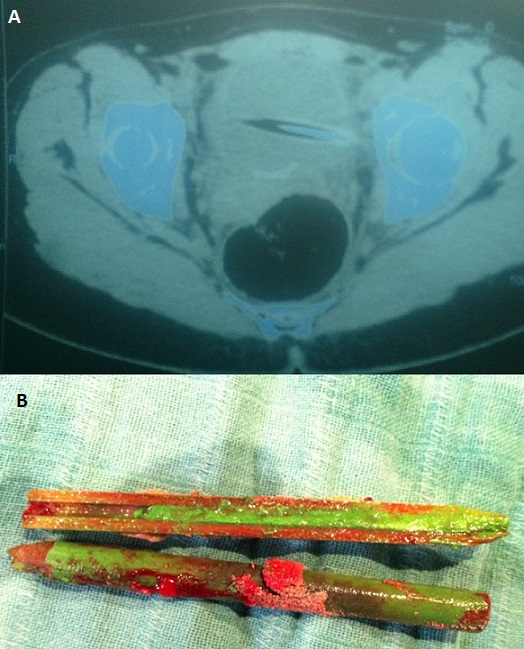

De nombreux articles de la littérature médicale rapportent des cas d'introduction de corps étranger dans la filière urogénitale. La plupart des cas sont associés à des désordres psychiatriques, à des cas de toxicomanie, ou dans un but de stimulation sexuelle. La vessie semble être un site inaccessible pour l'introduction de corps étranger surtout chez l'homme, cependant tous les objets concevables ont été insérés dans la vessie à travers l'urètre et chacun a posé des problèmes diagnostiques et thérapeutiques particuliers. Une jeune fille de 19 ans, s'est présentée aux urgences affirmant qu'elle s'est introduite il y'a 7 jours, dans un but érotique un crayon de couleur au niveau du méat. La patiente consciente, lucide, rapportait une notion d'hématurie et de douleur hypogastrique. L'examen clinique ne retrouvait pas le crayon au niveau du méat et ne montrait ni hématurie, ni contracture abdominale. Dans un but d'orientation diagnostique un arbre urinaire sans préparation a objectivé une opacité linéaire rappelant la forme d'un crayon se projetant sur l'aire vésicale, l'échographie vésicale après remplissage vésical a retrouvé une image hyperéchogène intravésicale confirmé par TDM mettant en évidence le crayon avec aspect longitudinale hyperdense effilé à son extrémité. Une cystoscopie pratiquée dans un but diagnostique et thérapeutique a permis de voir le crayon, de témoigner aussi de l'intégrité urétrale et vésicale et de retirer le corps étranger. La patiente fut adressée en consultation de psychiatrie pour avis et complément de prise en charge.